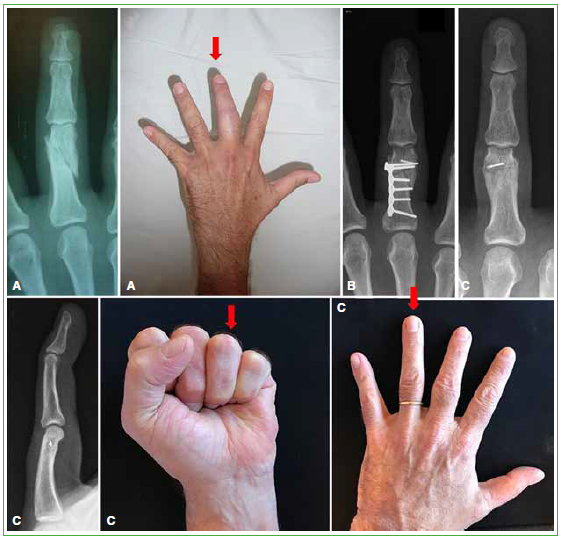

Materiales y Métodos: Se realizó un estudio retrospectivo que incluyó a pacientes con consolidación viciosa de falange tratados mediante osteotomía en el sitio de la deformidad, estabilizados con osteosíntesis rígida. Se registró la movilidad de los dedos. La valoración subjetiva consistió en el puntaje DASH y una escala analógica visual para el dolor en reposo, en actividad y la función.

Resultados: Doce pacientes (13 falanges) cumplieron los criterios de inclusión. El tiempo promedio entre la lesión inicial y la osteotomía fue 14 meses y el seguimiento promedio, 34 meses. La movilidad final promedio en flexo-extensión fue 89° metacarpofalángica, 74° interfalángica proximal, 54° interfalángica distal y la distancia pulpejo-palma, 3 mm. El puntaje promedio de la escala analógica visual en reposo fue 0; en actividad, 1 y la función promedio fue de 7 puntos; el puntaje DASH promedio fue 6. No hubo casos de seudoartrosis. Cinco pacientes requirieron el retiro de la placa. Los pacientes con osteotomía articular no presentaron signos de artrosis.

Conclusiones: La osteotomía de falange en el sitio de la deformidad es un procedimiento eficaz con un buen resultado objetivo y subjetivo a corto plazo. La utilización de placas y tornillos conlleva una tasa más alta de complicaciones; por lo tanto, los pacientes deben ser advertidos sobre la posibilidad de una segunda intervención quirúrgica.